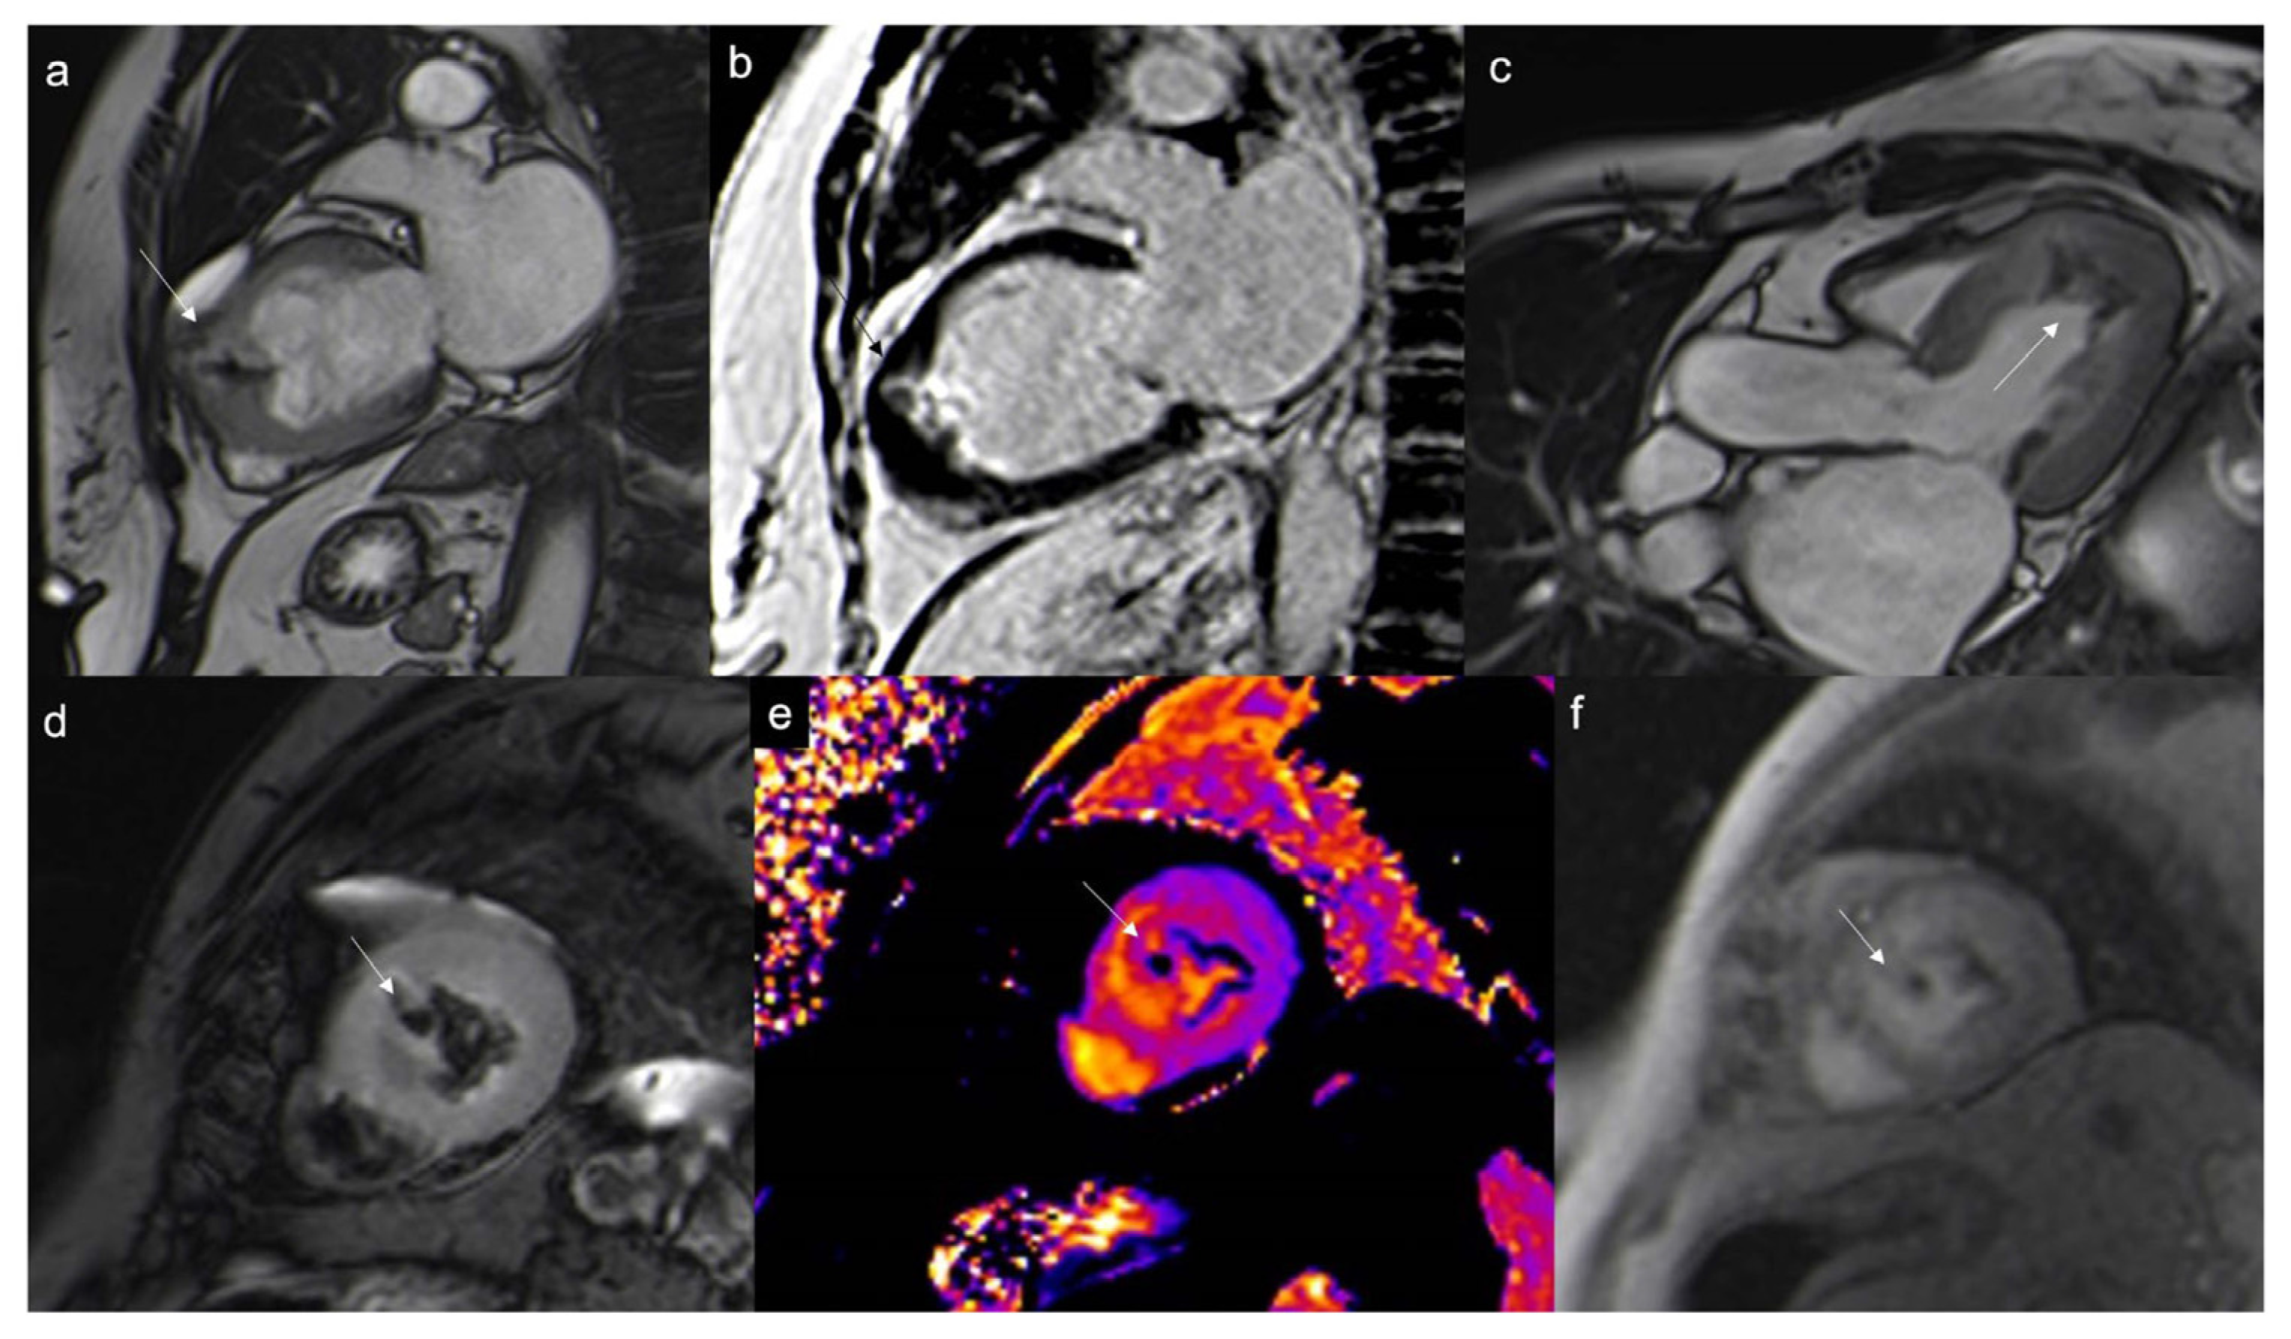

7.2.3. First-Pass Perfusion Sequences

- Assessment of vascularity

- Malignant masses often show heterogeneous enhancement; typically, angiosarcoma shows early avid enhancement as it is richly vascularized.

- Trombi due to their avascular nature appear non-enhanced.

7.2.4. Early Gadolinium Enhancement (EGE)

- Organized thrombi may show peripheral enhancement on LGE images, owing to their fibrous content.

7.2.5. Late Gadolinium Enhancement (LGE)